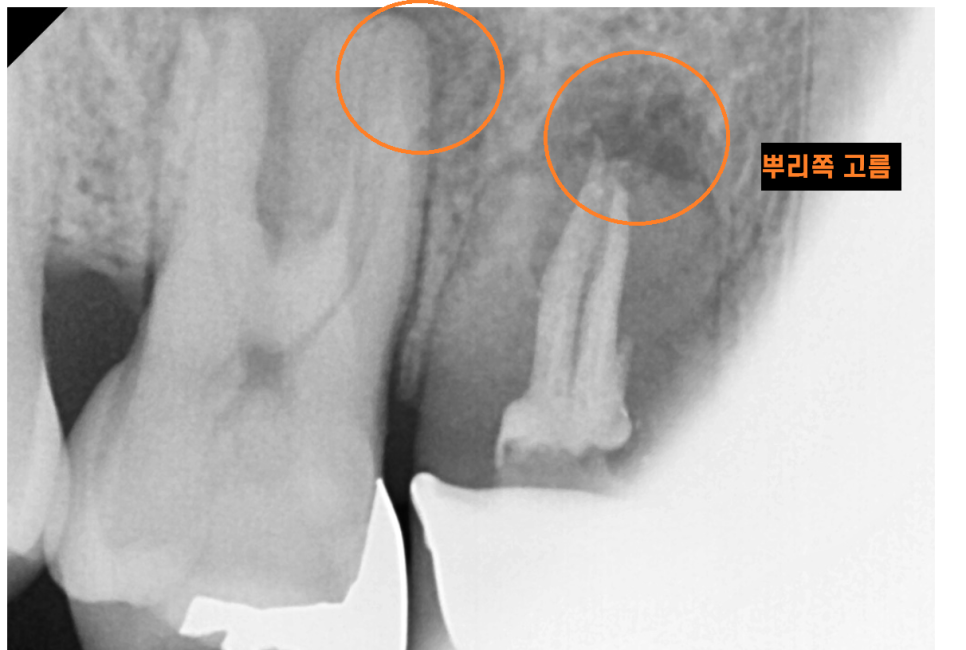

오른쪽 윗니 어금니 2개 상태가 많이 안좋습니다.

뿌리쪽에 고름이 있어서

잇몸뼈가 많이 녹았는지 주변보다 까맣게 보입니다.